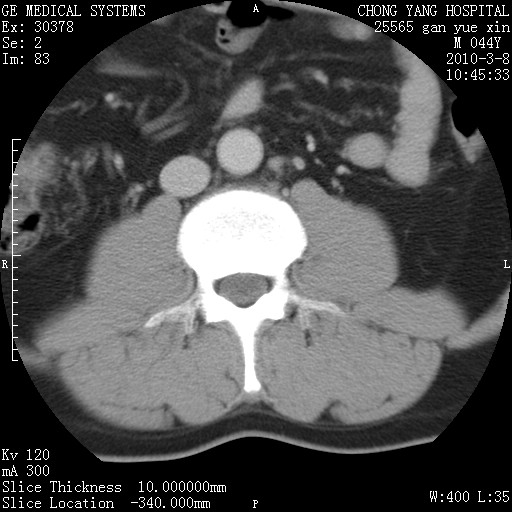

标题: CT24940:主动脉增强,典型病例。 [打印本页]

标题: CT24940:主动脉增强,典型病例。

夹层动脉瘤。

动脉夹层

夹层动脉瘤,典型

主动脉夹层。

动脉夹层的分型:

⒈debakey分型:根据主动脉夹层累及部位,分为三型:ⅰ型:原发破口位于升主动脉或主动脉弓部,夹层累及升主动脉、主动脉弓部、胸主动脉、腹主动脉大部或全部,少数可累及髂动脉。ⅱ型:原发破口位于升主动脉,夹层累及升主动脉,少数可累及部分主动脉弓。ⅲ型:原发破口位于左锁骨下动脉开口远端,根据夹层累及范围又分为ⅲa,ⅲb。ⅲa型:夹层累及胸主动脉。ⅲb型:夹层累及升主动脉、腹主动脉大部或全部。少数可累及髂动脉。

⒉stanford分型:a型:夹层累及升主动脉,无论远端范围如何。b型:夹层累及左锁骨下动脉开口以远的降主动脉。

夹层动脉瘤,少量胸水

夹层动脉瘤;左侧少量胸腔积液。

典型主动脉夹层。